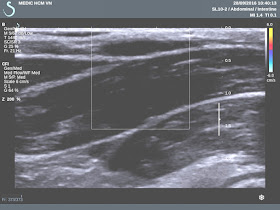

US scan at pubis detected

2 cystic masses  look like  double urinary bladder (US 1, transverse

scan ).